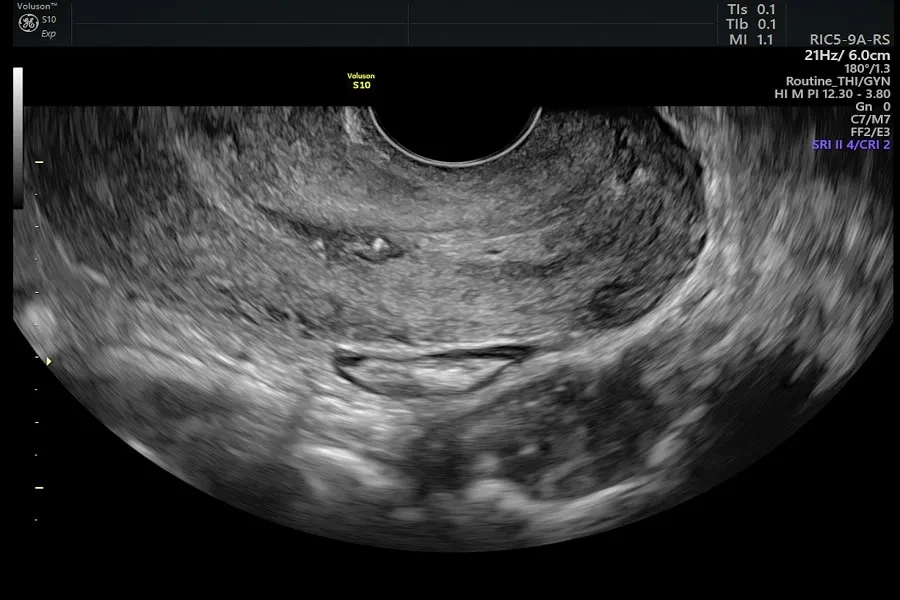

Siêu âm là phương pháp chẩn đoán hình ảnh an toàn, nhanh gọn, không dùng tia bức xạ và thường được sử dụng để đánh giá cơ quan sinh dục nữ. Kỹ thuật này có thể gợi ý những bất thường tại cổ tử cung như khối u, dày hoặc biến dạng mô. Tuy nhiên, siêu âm không thể xác định khối u là lành tính hay ác tính, nhất là ở giai đoạn sớm khi tổn thương còn nhỏ.

Siêu âm không phải là phương pháp chính để phát hiện ung thư cổ tử cung